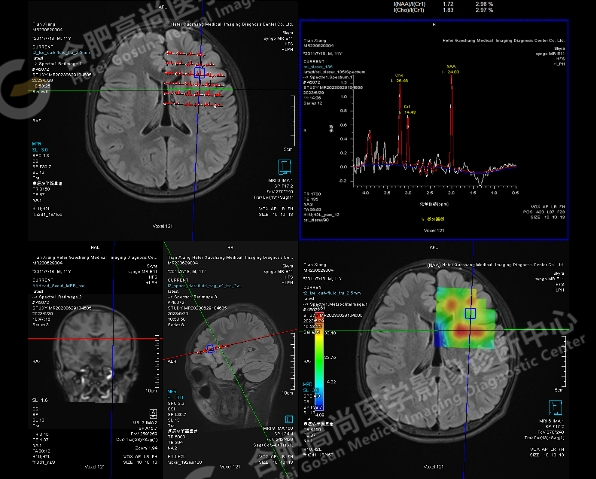

MRS 示:左侧病灶感兴趣区 NAA 24.83,Cho 26.46,Cr 14.43,NAA/Cr1 1.72,Cho/Cr1 1.83;右侧对照区 NAA 35.56,Cho 26.50,Cr 19.05,NAA/Cr1 1.87,Cho/Cr1 1.39。病灶提示神经元轻度减少。

加做 ASL 血流灌注显示左额叶病灶区局部灌注异常,呈稍高信号。

头颅 MRI 高分辨及功能成像:可用于进一步观察细微结构,也可利用功能成像,如,ASL 观察组织血流灌注情况,且无需静脉注射造影剂;MRS 可以敏感地测定局部脑区重要的代谢物浓度,从而反映病灶的病理改变,如 NAA 峰值降低提示神经元数目减少,Cr 和 Cho 峰值升高提示胶质增生。